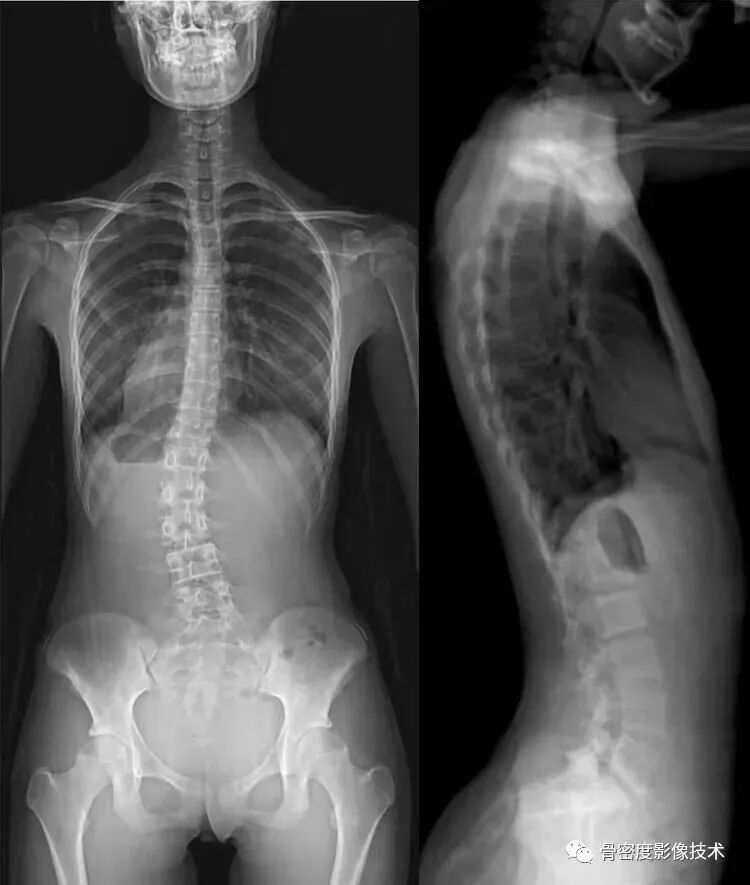

应用适应症:全脊柱摄影—青少年脊柱侧弯等畸形的矫正和人工腰椎椎间盘置换。可进行骨密度检查和负重全脊柱扫描。

图3 负重全景成像应用之全脊柱扫描技术